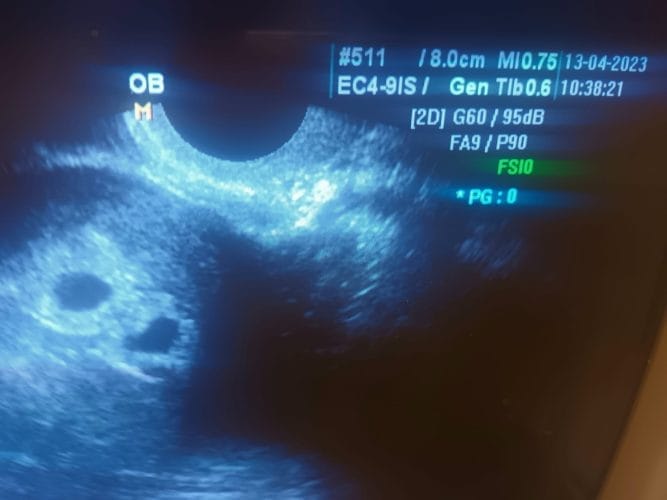

H Eυαγγελία έμαθε την Μεγάλη Πέμπτη ότι είναι έγκυος σε δίδυμα! Το υπερηχογράφημα που θα θυμάται για πάντα

H Eυαγγελία έμαθε την Μεγάλη Πέμπτη ότι είναι έγκυος σε δίδυμα! Το υπερηχογράφημα που θα θυμάται για πάντα! Το φετινό Πάσχα θα μείνει αξέχαστο στην Ευαγγελία που ανήμερα Μεγάλη Πέμπτη έμαθε ότι κυοφορεί τα διδυμάκια της. Το χαρμόσυνο νέο δημοσίευσε ο μαιευτήρας γυναικολόγος Δρ. Καλλιαντζής.